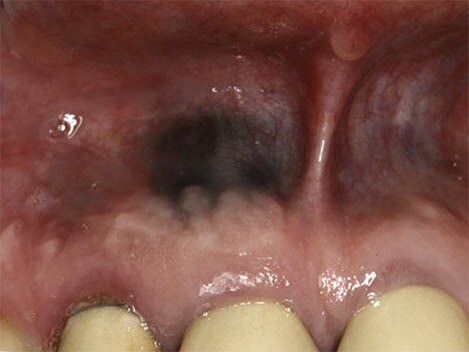

Oral Cancer

In rare cases, benign lesions that don't require treatment may transform into oral malignant melanoma, a type of oral cancer. A doctor will look at a range of factors to see if the lesion qualifies as melanoma. According to a research article published in the Journal of Indian Academy of Oral Medicine and Radiology, melanoma constitutes only 3–5% of all cutaneous malignancies, and oral melanoma is an aggressive neoplasm which accounts for less than 0.5%.

If you believe you have oral cancer symptoms, we recommend leaving the diagnosis up to the professionals and speaking to your doctor. If you exhibit symptoms, they may perform a biopsy (laboratory tests of your tissue) to confirm melanoma.